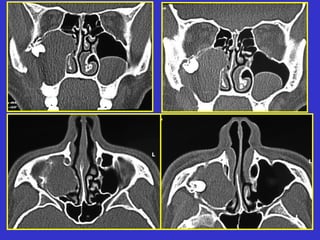

Este documento describe las diferentes proyecciones radiográficas utilizadas para examinar los senos paranasales, incluyendo las proyecciones básicas de Caldwell, Waters lateral y las proyecciones especiales como Hirtz y Waters mentonasal. También describe las diferentes estructuras anatómicas que componen el complejo ostiomeatal anterior y posterior de los senos paranasales.